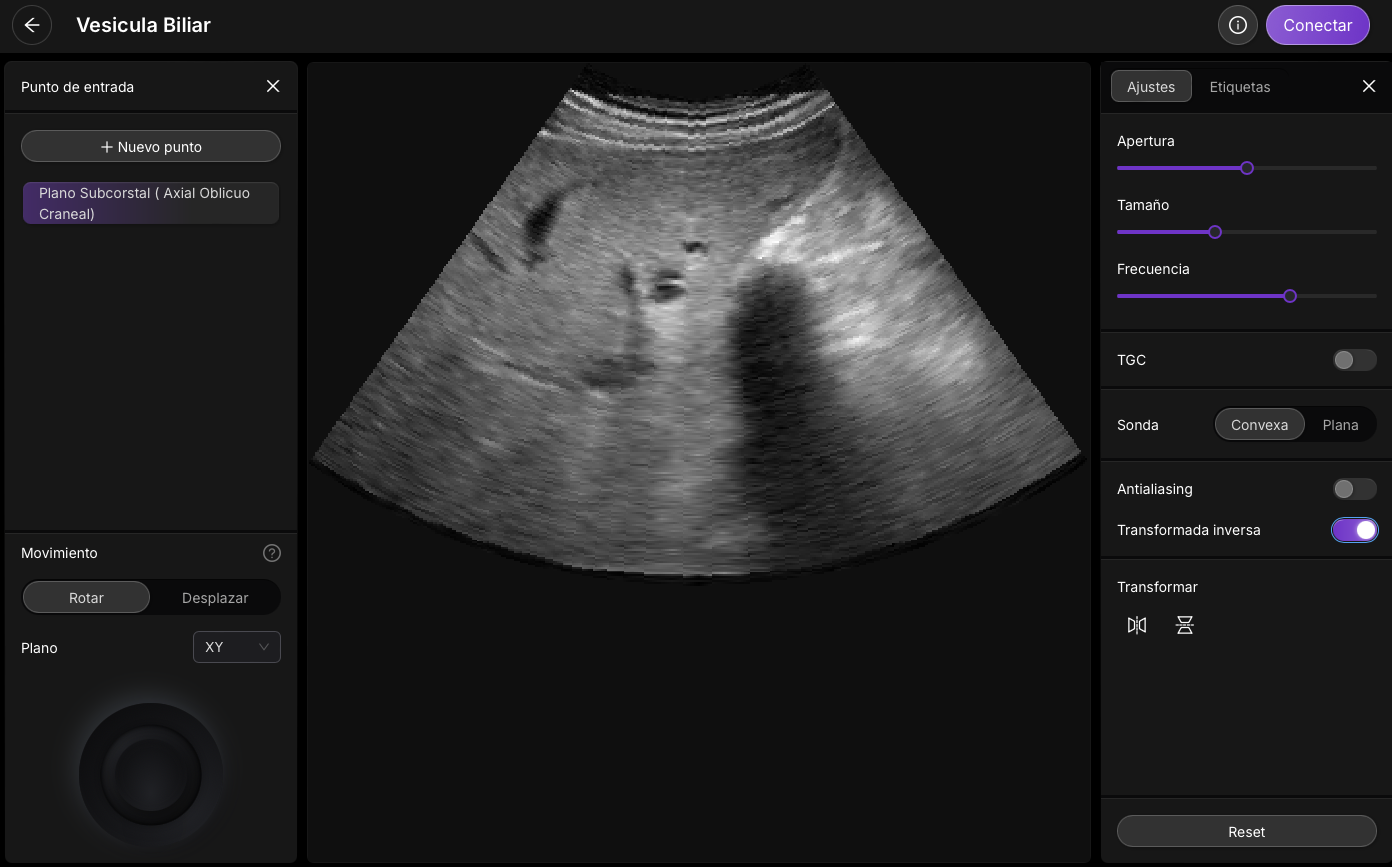

Procedimiento para Ecografía Abdominal

Corte Axial Subcostal Derecho e Inclinación Craneal

Este procedimiento está diseñado para evaluar la anatomía abdominal superior, enfocándose en el hígado, la vesícula biliar, el riñón derecho y las estructuras circundantes. Sigue estos pasos para obtener una imagen clara y precisa.

• Ubicación: Coloque el transductor debajo del arco costal derecho en sentido axial (horizontal).

• Inclinación: Incline el transductor hacia el lado craneal (hacia la cabeza) para obtener un ángulo óptimo.

• Frecuencia del Transductor: Seleccione una frecuencia de entre 3 y 5 MHz con un transductor convexo.

• Hígado: Examine su textura y ecogenicidad.

• Vesícula Biliar: Evalúe la pared y el contenido de la vesícula.

• Riñón Derecho: Identifique el riñón y observe su forma y ecogenicidad.